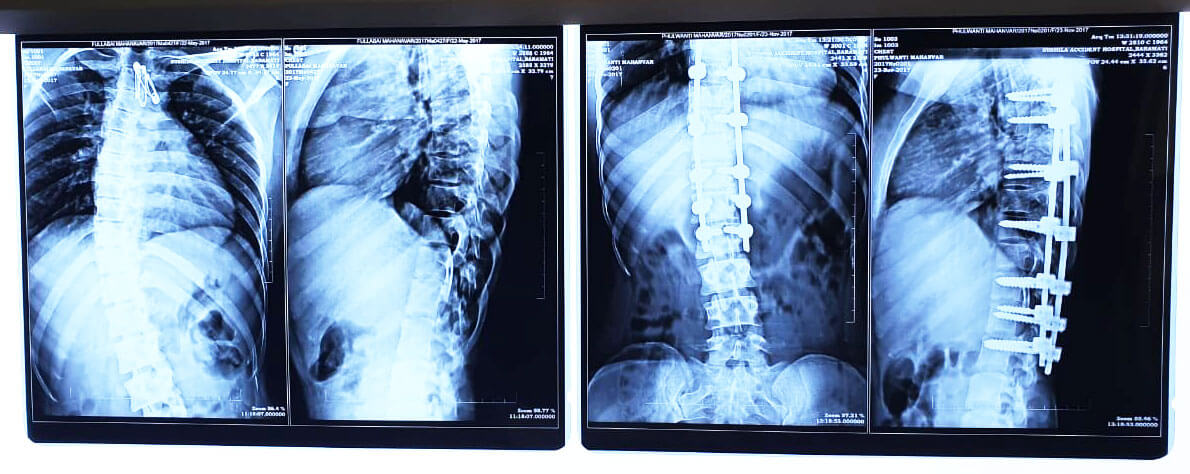

If you are looking for expert spine surgery in Baramati, Sushila Accident Hospital is your first choice. Under the experienced leadership of Dr. Gokul Kale, our hospital offers complete treatment for a wide range of spine-related conditions.

Dr. Gokul Kale and his team of highly skilled surgeons and medical professionals provide excellent care using the latest techniques in spine surgery and treatment. Dr. Kale’s extensive experience and commitment to patient care.

3. Focus on minimally invasive techniques

Whenever possible, our surgeons use minimally invasive techniques to treat spinal conditions. These techniques offer many benefits, including reduced pain, shorter hospital stays and faster recovery times. By minimizing the physical impact of surgery, we help patients return to their normal lives more quickly.

If you’re struggling with back pain, slip disc, or spine-related issues, don’t ignore the symptoms. Consult Dr. Gokul Kale, an experienced Spine surgeon in Baramati at Sushila Hospital, for accurate diagnosis and advanced treatment options. Take the first step toward a pain-free life—book your appointment today.